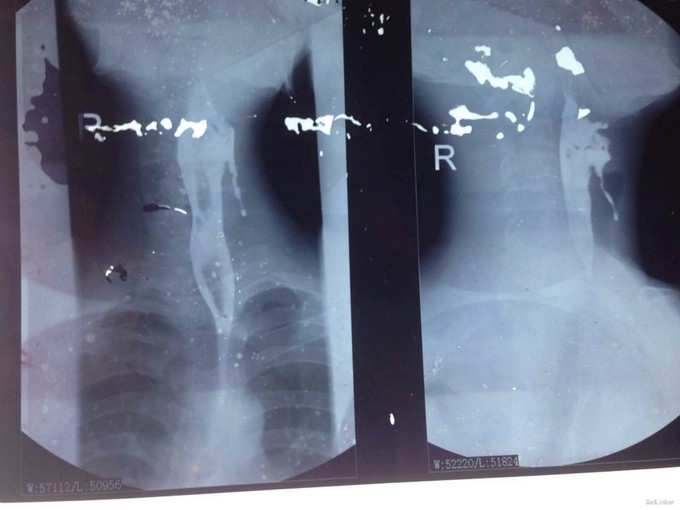

主诉:患者27岁男性,慢性起病,急性发作。因“反复颈部红肿、疼痛8年,再发1月”入院。 病史:该患者缘于8年前开始反复出现颈部红肿、疼痛、伴脓肿形成,8年前曾于当地医院反复行颈部脓肿切开引流术,术后好转,但反复发作多次;2008年12月该患再次颈部红肿、疼痛发作,并于当地医院就诊,行钡餐造影后考虑“食道瘘”,行手术治疗后好转,术后7年未再发作;1月前患者再次出现颈部红肿、疼痛,抗感染治疗后症状略好转,但1月来病情反复,逐渐加重;不伴呼吸困难、吞咽不适;无心悸、胸闷、气促,咳嗽;无多饮、多食、消瘦表现,无声音嘶哑或音调低沉,无多言、性情急躁、易激动等精神异常表现。门诊以"颈部脓肿?"收入普外科。患者自起病以来精神、胃纳、睡眠可,大小便正常,体重无明显变化。

查体:颈前有明显手术瘢痕,左侧颈外侧区可触及一约3cm×3cm大小肿物,质韧,边界不清,表面光滑,不可随吞咽上下移动,触痛明显,颈部未闻及明显血管杂音。 辅查:2015-11-16我院颈部增强CT示左侧颈部感染,多发脓肿形成。

该患者在诊断上是有些困难,颈部多发脓肿是明确的,但是瘘口的位置不好确定,从而未能确诊,8年前患者行上消化道钡餐检查,诊断“食管瘘”,但是我们从8年前的影像上看,瘘口的位置太高,不像是食管的瘘口,考虑是不是梨状窝的瘘道,为了进一步确诊,我们给患者行了胃镜检查,结果胃镜发现左侧梨状窝有1个3mm大小的小孔,胃镜未能通过,食管未见明显的瘘口。为了更加明确瘘口的位置,我们与影像科商议后决定口服造影剂后行颈部CT平扫,因怕钡餐沉积在脓肿内不好排出,我们采用了口服碘化油。此次影像明确了瘘口的确在左侧梨状窝。最终诊断:左侧颈部多发脓肿;左侧梨状窝瘘道形成。 治疗:入院后予抗感染、禁食、营养支持等治疗,患者感染得以控制,请耳鼻咽喉科会诊后建议转科治疗。